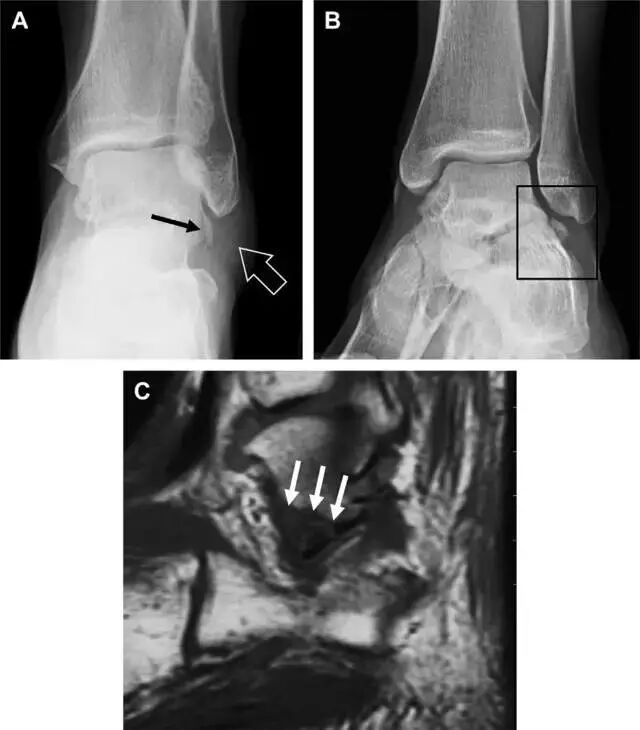

首先,来看踝关节骨折的高危区(图 1)。

图 1 踝部探查模板。阅片时,需对踝关节的前后位片(A)、内旋转位片(B)侧位片(C)仔细阅读,逐一详细排查。上图中的骨折:1. 内踝骨折,2. 外踝骨折,3. 胫骨结节骨折,4. 胫骨后踝骨折,5. 距骨骨软骨骨折,6. 距骨外侧突骨折,7. 距骨后突骨折,8. 距骨舟骨关节背侧骨折,9. 跟骨前突骨折,10. 跟骨骨折嵌插入趾短伸肌,11. 第五跖骨底骨折